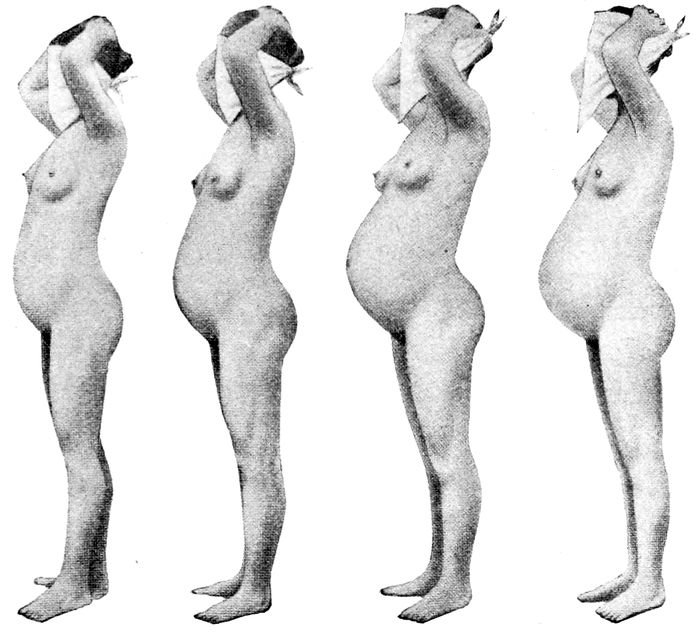

Fig. 27.—Abdominal enlargement at third, sixth, ninth, and tenth months of pregnancy. (Williams.)